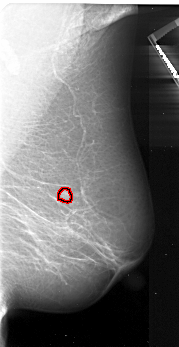

A_1048_1.RIGHT_MLO

RIGHT_MLO LINES 4846 PIXELS_PER_LINE 2506 BITS_PER_PIXEL 16 RESOLUTION 42 OVERLAY

FILE: A_1048_1.RIGHT_MLO.OVERLAY

TOTAL_ABNORMALITIES 1

ABNORMALITY 1

LESION_TYPE MASS SHAPE IRREGULAR MARGINS ILL_DEFINED

ASSESSMENT 4

SUBTLETY 5

PATHOLOGY MALIGNANT

TOTAL_OUTLINES 1

BOUNDARY